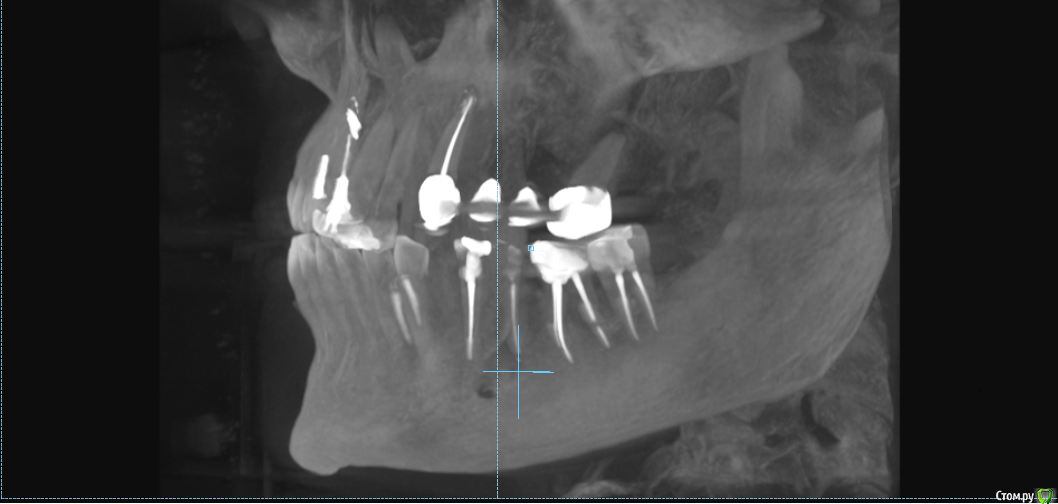

msa Опубликовано 27 февраля, 2019 Поделиться Опубликовано 27 февраля, 2019 Здравствуйте, уважаемые доктора!Прошу совета в выборе оптимального плана лечения и восстановления зубного ряда.Слева вверху (2.3-2.6) мост м/к с 1998 г(со слезами обточила здоровый красивый клык).Справа внизу был мост м/к 2006г на 4.4-4.7 (опорный моляр 4.7 + штифт в 4.5, конструкция была не очень, т.к. не отдала обтачивать под коронку клык 4.3) Через 7 лет мост слетел… От слова совсем.В н/вр пытаюсь понять, нужно ли бороться за премоляр 3.5 Или однозначно удалять? Можно ли сохранить 3.6 с помощью культевой вкладки?Какие варианты оптимального замещения низа справа 4.4-4.7? Корни пока не удаляю. Жизнеспособен ли верх 1.4-1.6? (пломбам больше 20 лет) Скриншоты из КТ от 25.02.19 ОПТГ не делалаСпасибо!С уважением, Марина Ссылка на комментарий

msa Опубликовано 27 февраля, 2019 Автор Поделиться Опубликовано 27 февраля, 2019 (изменено) Нужна ОПТГ или панорамный срез из КТ Получилось немного кривоватокрупно Изменено 27 февраля, 2019 пользователем msa Ссылка на комментарий